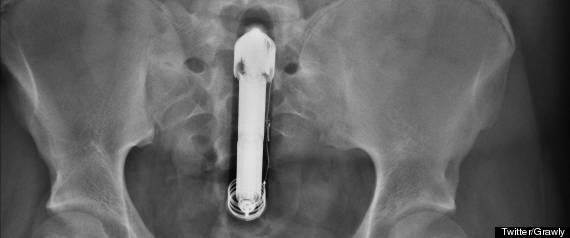

按摩棒卡菊花苦撑5天,单身宅男“不好意思就医”身亡

英国一名与母亲同住的无业男子有一天自己在家裡玩按摩棒,一不小心滑入屁眼拔不出来,他觉得很丢脸不好意思告诉别人,就这样一个人躺在沙发苦撑5天,终于在友人的哀求下同意前往医院求助,无奈他插得太深已病入膏肓,按摩棒拔出来两个月后仍死于腹部创伤造成的败血性休克。

由于这名男子的死因很特别,英国地方法院为了釐清责任特别召开了一次听证会,才让此事曝了光,「威利斯先生的朋友看到他头晕无力、整整5天躺在沙发上动也不动,不顾反对坚持叫救护车将他送医。」医院顾问除了向法官说明整起事情的来龙去脉,还当庭念了一份死者威利斯先生的声明,「我拔不出来那根插在我直肠裡的振动器。」